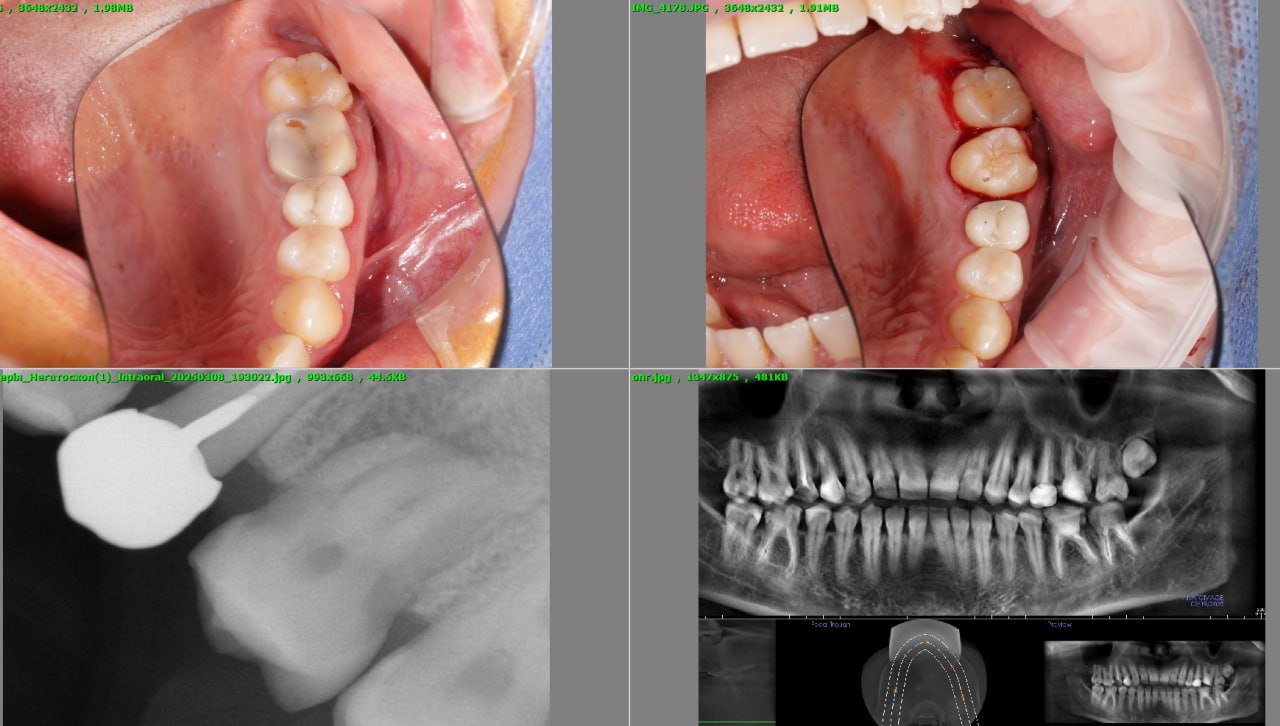

Як відбувається пересадка зуба

- КТ-діагностика

- Атравматичне видалення

- Пересадка

- Фіксація

- Контроль

Клінічний кейс

Пацієнт, 35 років. Втратив 6-й зуб. Імплантацію не хотів.

Було проведено трансплантацію за один візит. Через 6 місяців — повне приживлення. Через 1,5 року — ідеальний результат.